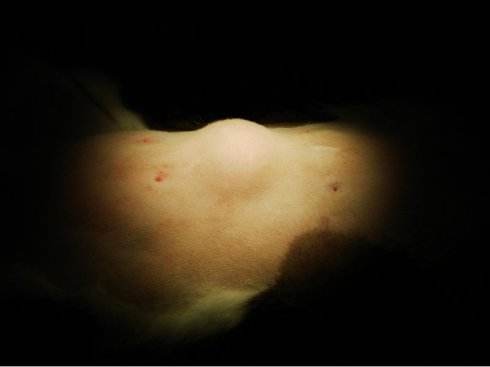

脂肪瘤生长变大的额速度非常慢,可以长在身体的任何部位,但最常见的是躯干和四肢。大多数情况下是一个孤立的包,极少数情况下会有好几个,尤其是存在遗传性疾病,比如家族性多发性脂肪瘤病时。

绝大多数情况下,脂肪瘤不疼也不痒,但极少数的脂肪瘤(血管脂肪瘤)会有疼痛感。位置比较浅的脂肪瘤肉眼就能看出来,摸起来一般比较软,大多是圆形或椭圆形,有大的也有小的。

再比如:后背或屁股上长了脂肪瘤,你躺着或坐着一旦压着搁着瘤体时,总会觉得不舒服。而且反复刺激可能还会加速瘤子长大。